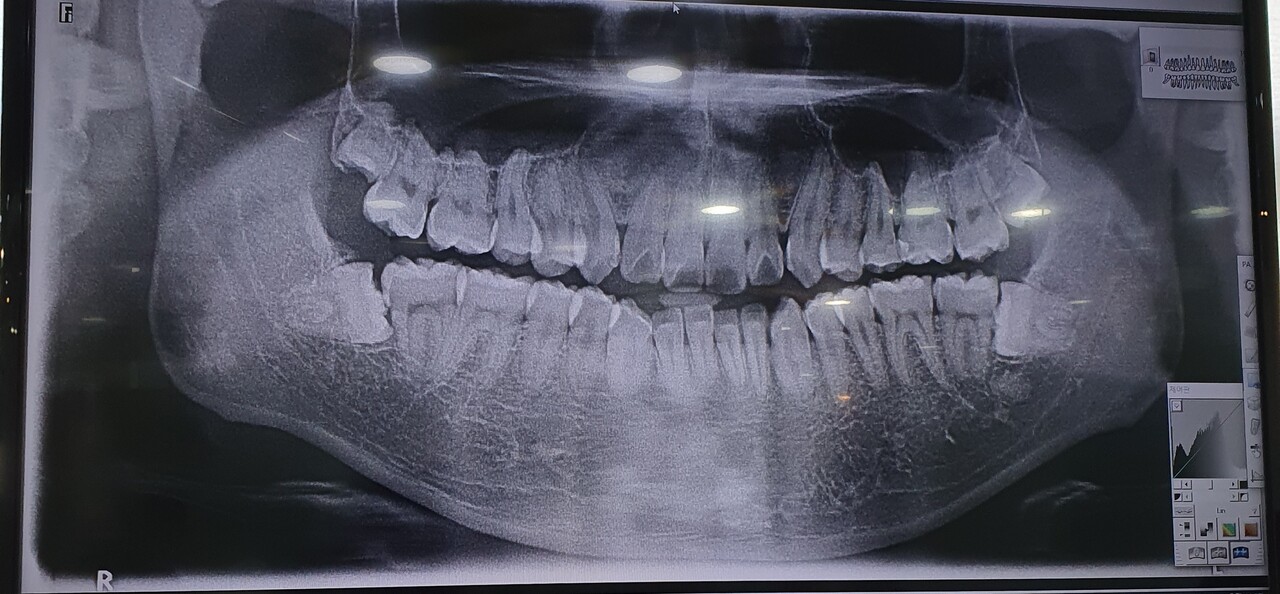

사랑니에 대해 많은 화제가 있는데 가장 궁금한 것 중 하나가 사랑니를 무조건 빼야 하는지, 아니면 그냥 놔둬도 되는지 입니다. 사랑니는 정상적인 치아처럼 정상적으로 자라면 큰 문제가 없으나, 사랑니가 불규칙하게 자라거나 인접치아와의 맞물림이 고르지 못한 경우 잇몸과 사랑니 사이에 음식물이 끼기 쉬워 충치 및 안 좋은 호흡. 제때 제거하지 않으면 턱 신경을 손상시켜 염증, 통증, 부기를 유발할 수 있습니다. 할 수 있다고 합니다. 칭량리치과에서는 사랑니가 정상적인 맹출기간이 지나도 맹출하지 않으면 사랑니가 자랄 수 있다고 밝혔습니다. 매복 사랑니라면 미리 엑스레이 검사를 통과하고 적절한 때에 치료를 받는 것이 가장 좋다. 사랑니를 제대로 발치하지 않으면 사랑니가 다양한 형태로 자라게 되는데, 매복 사랑니도 완전 매복이 될 수 있고, 반 매복이 되는 경우도 많습니다. 치아를 절단하여 발치해야 하는데 이때 신경을 제대로 건드리지 않거나 수술 후 적절한 사후관리를 하지 않으면 감염이나 염증 등의 다른 질환을 유발할 수 있어 주의가 필요합니다. , 일반 X-In RAY는 눈에 보이지 않는 혈관과 신경을 3D CT로 확인할 수 있으며, 혈관과 신경을 보다 세밀하게 치료할 수 있다고 합니다. 손상이 발생할 수 있는 부위를 줄이면서 치료를 진행하기 때문에 안정적인 발치가 가능하다고 합니다. 구강악안면외과 전문의에 의한 사랑니 발치 칭량리치과에서는 구강악안면외과 전문의가 사랑니 발치를 시행하고 있습니다. 구강악안면외과의는 입, 턱, 얼굴 등의 모든 부분을 치료합니다. 풍부한 임상 경험과 구강 구조에 대한 이해로 구강 내 염증, 손상, 기형 등 다양한 질병을 정확하게 진단하고 난해한 경우도 치료할 수 있습니다. 발치가 어려운 매복 사랑니도 청량리치과의원에서 안정적으로 발치를 할 수 있으니 미리 확인하시고 적절한 치료 계획을 세우시기 바랍니다. 50m NAVER Corp. More/OpenStreetMap Map Datax NAVER Corp./OpenStreetMap Map Controller Legend Real Estate Street 군면동시군구시군 제이치과의원 동대문구 이문로 37 베라체캠퍼스 308호 서울 광고 이후 계속. 다음 주제작가 취소 Qingliangli 치과 재생 0 좋아요 0 좋아요 공유 0:00:00 재생 음소거 00:00 00:00 실시간으로 전체 화면 해상도 설정 currentTrack 자막 재생 속도 비활성화 NaNx 해상도 자막 설정 옵션 비활성화 텍스트 크기 배경색 재생 속도 0.5 x 1.0x(기본값) 1.5x 2.0x 알 수 없는 오류가 발생했습니다. 도움말 보기 음소거되었습니다. HD로 재생하려면 이 동영상에 라이선스를 부여하세요. 설정에서 해상도를 변경해 보세요.더 알아보기 0:00:00 축소/확장 Qingliangli Dental Clinic #凉凉里室室室